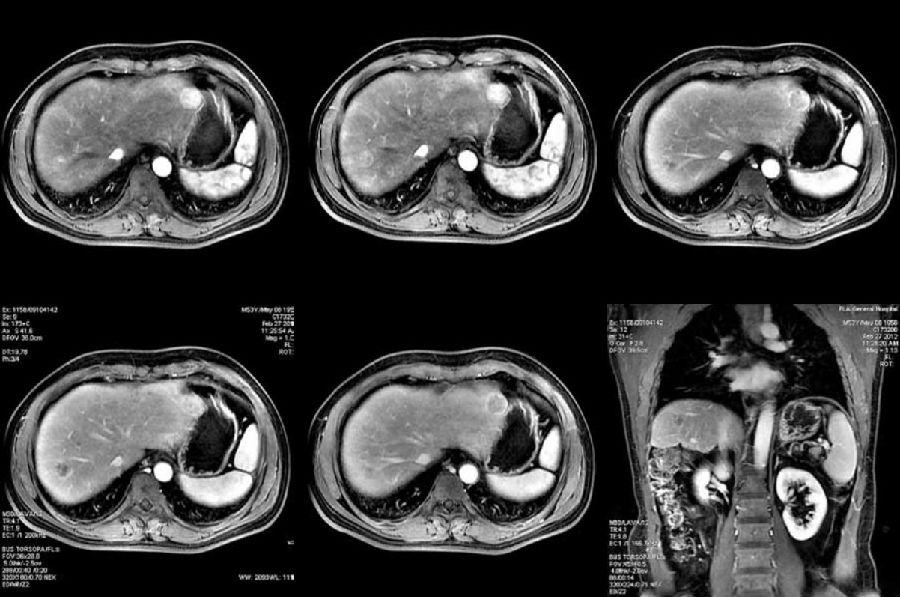

病史: 男,53岁。乙肝病史10余年。超声检查显示弥漫性肝硬化改变。

扫描序列: GE LAVA Flex多期动态增强扫描;T2脂肪抑制;DWI

MR影像及表现:

T2脂肪抑制图像,清晰显示肝实质内存在大量环状低信号改变,这是肝硬化所导致的硬化结节的典型表现;同时还可见两类圆形高信号病灶

弥散图像显示相应病变呈高信号

LAVA Flex多期动态增强扫描,显示病灶在动脉期强化但在静脉期及延迟期强化消退。

影像分析: 平扫T2图像:充分显示了磁共振在软组织对比分辨率上的优势,更敏感的显示肝硬化所导致的硬化结节。当硬化结节发展演变为癌前病变及肝细胞肝癌时,因为动脉供血增多、肝血窦容积增大以及肿瘤血管增多等改变,导致病灶内血容量增多,血流速度缓慢,从而导致T2弛豫时间延长,因而这类病变在T2相可以表现为高信号改变。 弥散成像:可以敏感检测到病灶内水分子扩散异常,能更敏感的发现小肝癌病变。 LAVA Flex 多期动态增强:病灶在动脉期强化,提示病变以动脉供血为主,这是肝硬化再生结节向不典型增生结节及肝细胞肝癌转变过程中的一个重要病理改变;而静脉期及延迟期病灶强化消退提示相应病灶门脉供血减少,这实际上是鉴别高度不典型增生结节(High Grade Dysplastic Nodule, HGDN)和肝细胞肝癌另一个重要依据。

最后诊断: 肝硬化合并小肝癌

技术点评: 在肝硬化相关结节的演变发展过程中,从再生结节到不典型增生结节再到肝细胞肝癌,所伴随的一个重要病理改变是血供类型的改变。从正常以门静脉供血为主,逐步发展到以肝动脉供血(新生肿瘤血管)为主。肝硬化相关结节演变过程中所伴随的血供类型的改变为影像学检查明确结节性质提供了可能。 本病例中,LAVA Flex多期动态增强扫描显示相应病灶在动脉期强化,提示病变以动脉供血为主,这是肝硬化再生结节向不典型增生结节及肝细胞肝癌转变过程中的一个重要病理改变;而静脉期及延迟期病灶强化消退提示相应病灶门脉供血减少,这实际上是鉴别高度不典型增生结节(HGDN)和肝细胞肝癌的另一个重要依据。

病例来源:解放军总医院